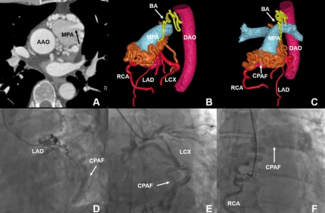

Leizhi Ku, MD; Yuhang Wang, MD; Zheng Liu, MD; Xiaojing Ma, PhD

A 7-year-old girl presented with cyanosis for the past 4 years. Physical examination revealed digital clubbing and cyanosis, and a rest arterial oxygen saturation level of 82%.

11/27/2024

Journal of Invasive Cardiology